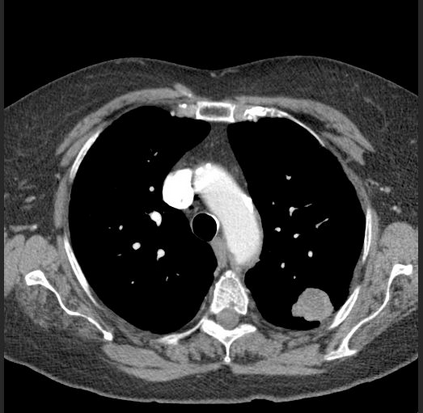

The evaluation of infectious disease processes on radiologic images is an important and challenging task in medical image analysis. Pulmonary infections can often be best imaged and evaluated through computed tomography (CT) scans, which are often not available in low-resource environments and difficult to obtain for critically ill patients. On the other hand, X-ray, a different type of imaging procedure, is inexpensive, often available at the bedside and more widely available, but offers a simpler, two dimensional image. We show that by relying on a model that learns to generate CT images from X-rays synthetically, we can improve the automatic disease classification accuracy and provide clinicians with a different look at the pulmonary disease process. Specifically, we investigate Tuberculosis (TB), a deadly bacterial infectious disease that predominantly affects the lungs, but also other organ systems. We show that relying on synthetically generated CT improves TB identification by 7.50% and distinguishes TB properties up to 12.16% better than the X-ray baseline.